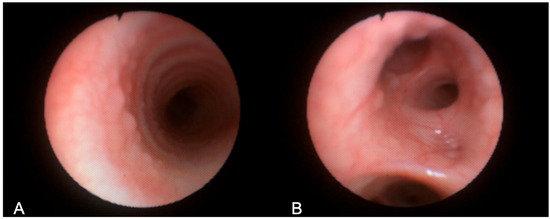

3.1. Patient 1

| 30, M | F508del/ E585X | SA, PA | 73 | 36 | 2, 10 mm, right posterolateral at T2 level | Yes | Visible radiologically and endoscopically | Bronchoscopy after 6 months: stable TD; occurrence of punctiform paracarenal TD |